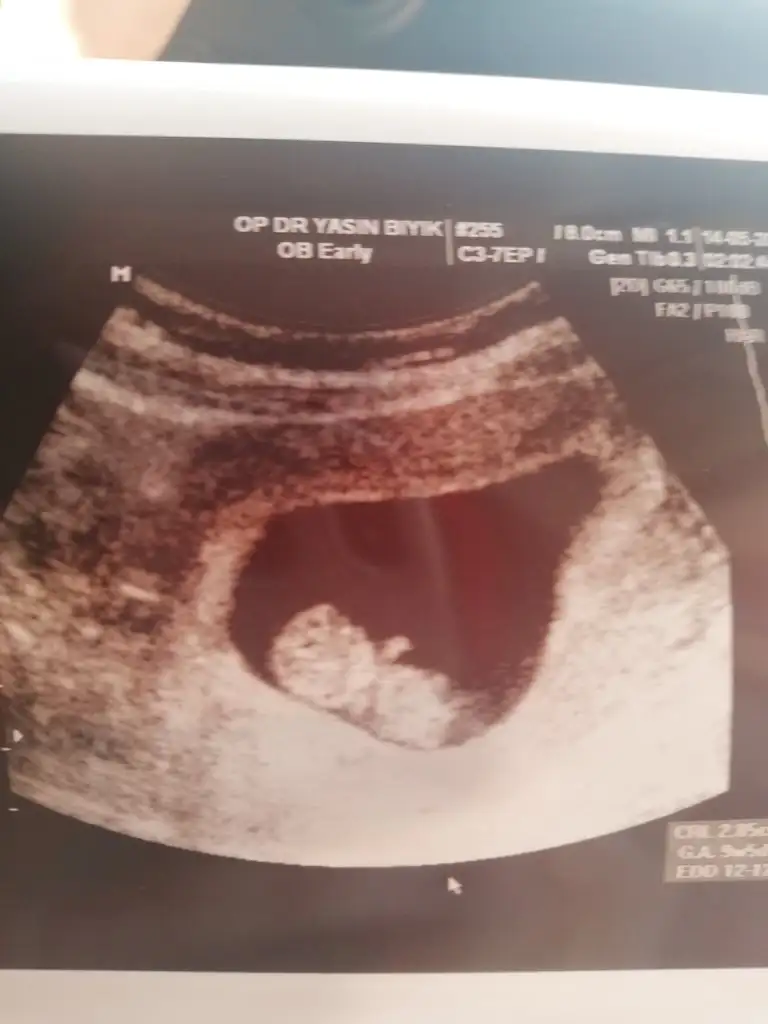

Kızlar ben de 10. Haftamdayım bana da tahminde bulunabilir misiniz